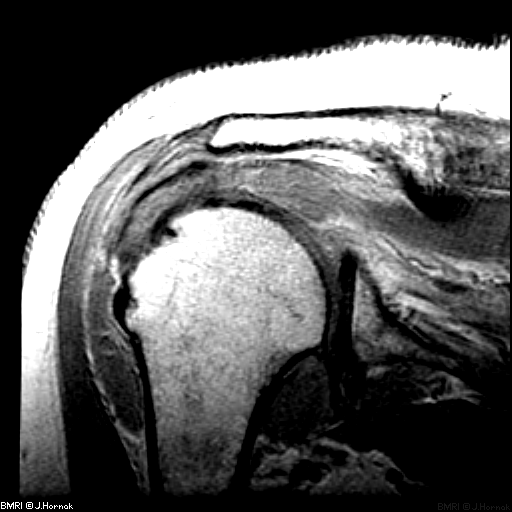

- Конечности